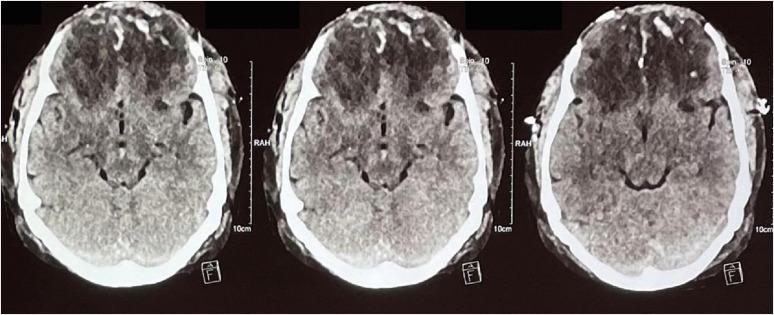

Farm-related head injuries are a significant cause of death and disability in rural households. Traumatic brain injury can result in long-term disability. The use of modern farming equipment has increased in the Indian agricultural sector over the last few decades. Machines such as threshers and winnowing devices can cause open skull fractures or scalp avulsions, while the fall of heavy tools may lead to severe head trauma. Farm animals such as bullocks and horses can also inflict traumatic brain injuries with their pointed horns, through trampling, kicking, or rarely biting. We present a case series of four patients who sustained head injuries due to farm-related accidents. All patients sustained compound cranial fractures with underlying brain parenchymal injuries, and three of them achieved complete recovery following timely medical intervention.

与农场相关的头部损伤是农村家庭死亡和残疾的一个重要原因。创伤性脑损伤可导致长期残疾。在过去几十年里,印度农业部门现代农用设备的使用有所增加。脱粒机和扬谷设备等机器可导致开放性颅骨骨折或头皮撕脱伤,而重型工具掉落可能导致严重的头部创伤。公牛和马等农场动物也可能用它们的尖角、通过踩踏、踢踹或极少情况下的撕咬造成创伤性脑损伤。我们报告了一系列4例因与农场相关的事故而头部受伤的患者。所有患者均发生复合性颅骨骨折并伴有潜在的脑实质损伤,其中3例经及时医疗干预后完全康复。